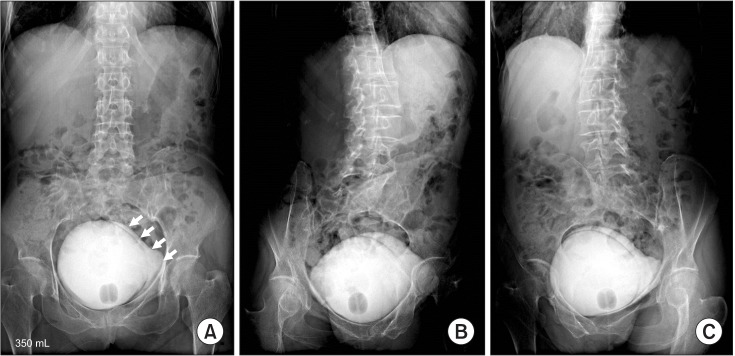

عکس رنگی مثانه در عکس رنگی مثانه ماده حاجب به صورت ترکیبی با نرمال سالین از طریق سوند وارد مثانه بیمار میشود، و گرافی های متعدد در شرایط پربودن مثانه، و حین ادرار کردن از بیمار گرفته میشود و مسیر خروجی ادرار بررسی میشود.

عکس رنگی مثانه در عکس رنگی مثانه ماده حاجب به صورت ترکیبی با نرمال سالین از طریق سوند وارد مثانه بیمار میشود، و گرافی های متعدد در شرایط پربودن مثانه، و حین ادرار کردن از بیمار گرفته میشود و مسیر خروجی ادرار بررسی میشود.